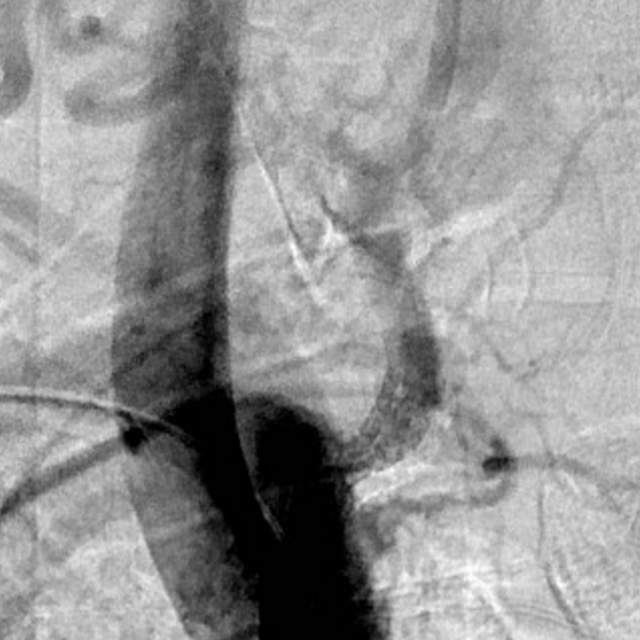

最近,儿子带老人家过来复查,检查发现右侧椎动脉起始部的狭窄越来越重,和9个月前相比,简直判若两人(管),左侧椎动脉又先天发育不好……,看来保守治疗吃药不太行,还得需要外科干预

和家属商量后,我们采用全球首款椎动脉专用药物洗脱支架(Maurora)成功精准切线位植入,消除了这个“卡脖子”的狭窄……

术后随访结果:老人家说话口齿清晰了,思维反应也快了……